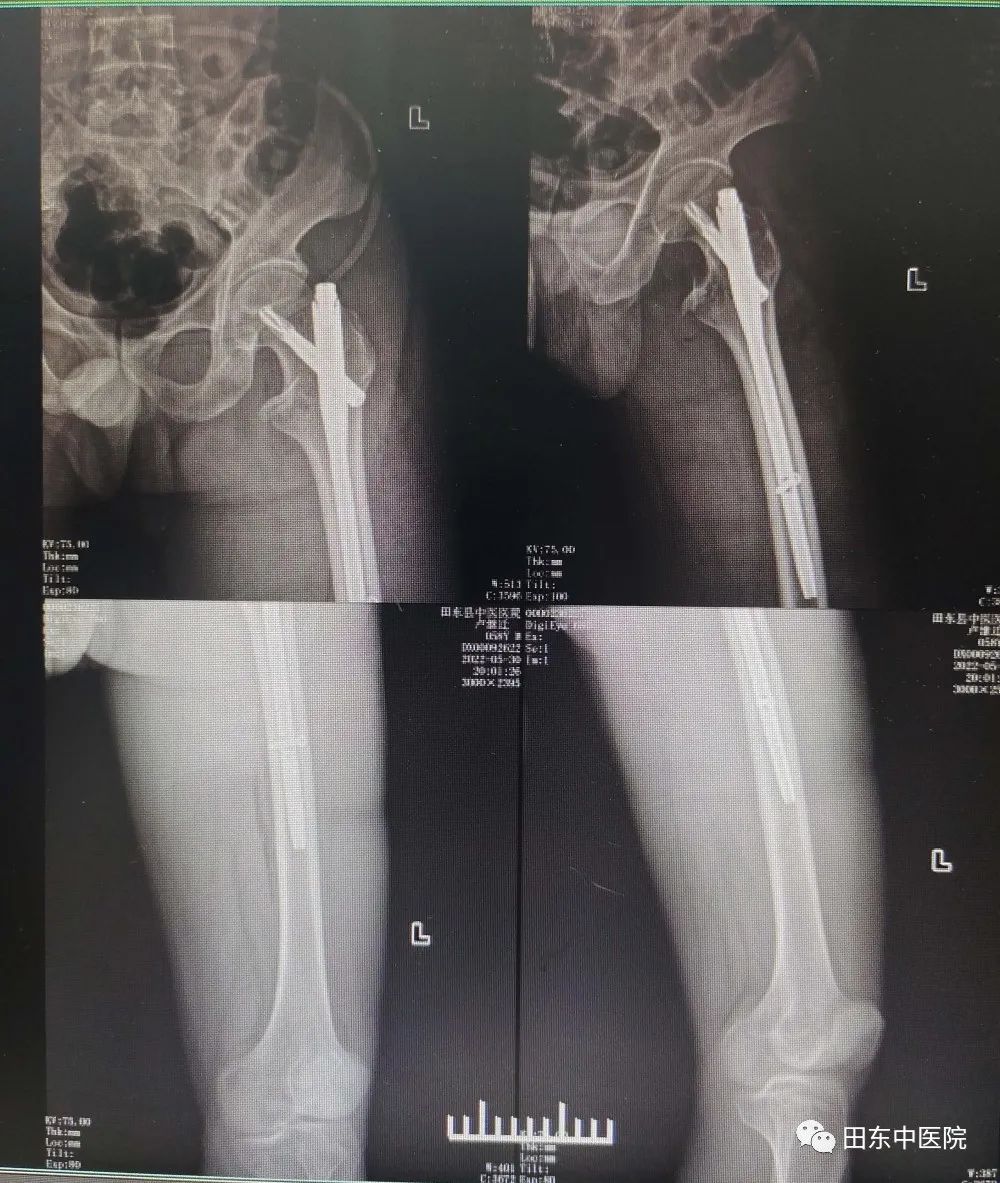

经过骨伤科医护团队的精心准备,入院后第五天患者调整为最佳手术状态。5月29日,患者在腰麻硬膜外联合麻醉下行左股骨粗隆间骨折闭合复位PFNA内固定术,在骨伤科手术团队的沉着应对与麻醉科、手术室密切配和下,顺利完成了手术。术后影像显示:左侧股骨粗隆断端对位、对线良好,内固定满意。同时在护理团队的精心护理下,实现患者快速康复,患者已经扶拐下床适当活动。

▲术后影像